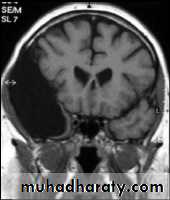

Coronal T1-weighted MRI image through a brain lesion showing homogeneity of the lesion, lack of a perceptible wall, lack of internal complexity, and CSF signal intensity. There is associated remodeling of the adjacent calvarium and brain displacement. These imaging features are typical of an arachnoid cyst.

Axial T2-weighted MRI image through the midbrain, showing a right middle cranial fossa homogeneous lesion) with CSF signal intensity and no perceptible wall or internal complexity. There is associated remodeling of the adjacent sphenoid bone and brain displacement..